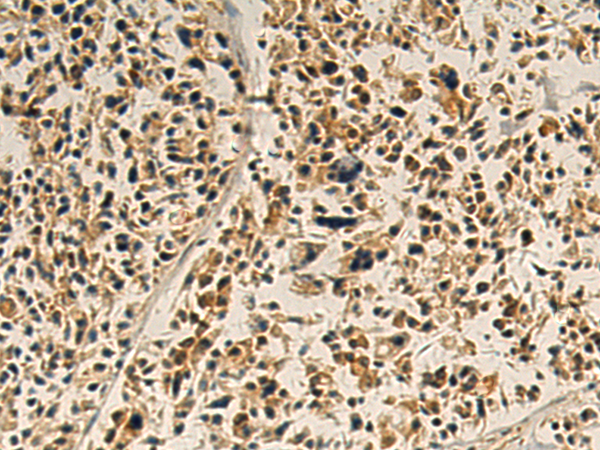

The image is immunohistochemistry of paraffin-embedded Human ovarian cancer tissue using P03519(GSDMA Antibody) at dilution 1/115. (Original magnification: ×200) |